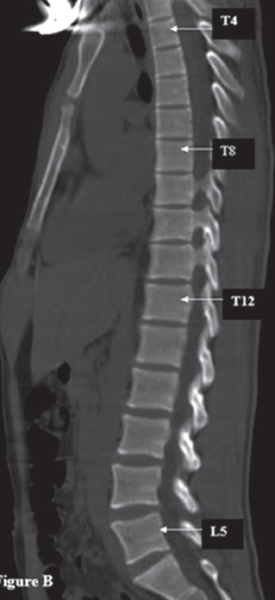

평면등입니다. 편평한 등은 허리, 즉 흉추의 증상만을 의미하는 것이 아닙니다. 복잡한 변화 패턴으로 나타날 것입니다. 요추에는 소위 곧은 요추(straight lumbar)가 진행되는 반면, 이러한 상호작용으로 인해 흉추의 C-curve가 축소된다. 동시에 경추 또는 경추가 곧게 펴지면서 곧게 되거나 앞으로 이동하게 됩니다. 요추와 경추의 정렬도 디스크 진행과 관련이 있습니다. 일반적으로 경요추(translumbar spine)가 곧게 펴짐에 따라 후방디스크(retrodiscal annulus)에 가해지는 압력이 증가하여 디스크가 더 쉽게 형성됩니다. 또한 제가 말씀드리고 싶은 것은 우리의 척추가 영향을 받는 규칙성입니다. 우리 몸의 척추에는 3개의 곡선이 있습니다. 세 가지 곡선이 있습니다: 경추와 요추를 위한 역C 곡선과 흉추를 위한 C 곡선. 곡선이 직각으로 배치되면 신체에 미치는 영향을 1/n^3 +1 또는 1/10로 줄일 ​​수 있습니다. 하나씩 무너지면 n의 수가 줄어들고, 척추의 만곡이 모두 사라지면 모든 충격을 받는다. 이는 후유증, 만성 허리 및 경추 통증, 단순 염좌와 같은 질병에서도 쇼크가 오랫동안 지속될 수 있음을 의미합니다. 이러한 이유로 미학적 관점에서만 자세의 불균형이나 나쁜 자세를 걱정해서는 안 됩니다. 로커는 보통 더 발전된 형태의 플랫백을 의미합니다. 뒤로 기울어진 골반은 점점 심각해졌고 곧은 목은 거북목이 되었다. 이러한 자세는 일상생활에서 만성통증을 유발할 수 있어 빠른 치료가 필요합니다. 치료는 기본적으로 한의원에 가셔서 ‘종나법’을 고려하시면 됩니다. https://blog.naver.com/zinsimzs/222976550263